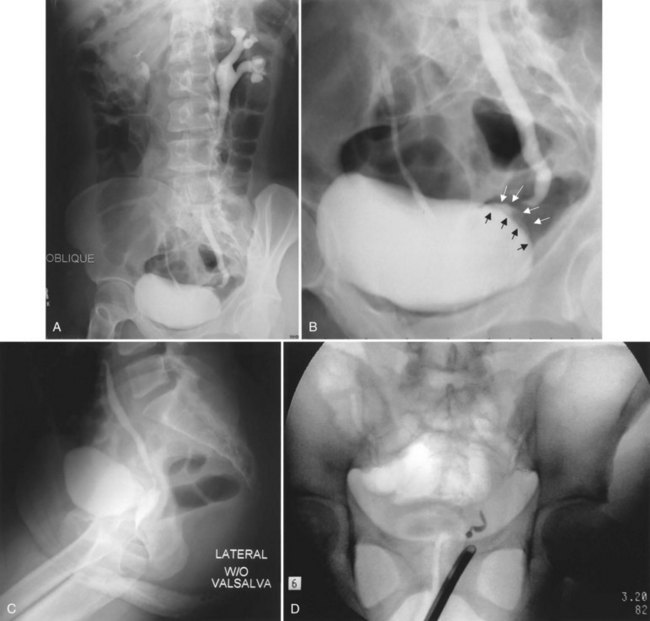

A cystogram and/or voiding cystourethrogram (VCUG) and an upper tract study should be performed in patients being evaluated for a VVF. The cystogram may objectively determine the presence and location of the fistula. Upon filling of the bladder, contrast often begins to opacify the vagina, almost immediately confirming the presence of a VVF. VVF are often best seen in the lateral projection (Fig. 77–7) in which the bladder and vagina are not superimposed. Often, the actual VVF tract may be visible in the lateral projection (Fig. 77–8). However, voiding images may be necessary in some patients with small fistulae, to demonstrate the VVF. The slight increase in intravesical pressure that accompanies micturition is usually adequate to demonstrate even very small fistulae. Importantly, a cystogram that fails to demonstrate a suspected VVF, but lacks voiding images or postvoid images, should be considered nondiagnostic. During voiding, care should be taken to exclude vaginal voiding or reflux of contrast from the introital region cephalad into the vagina, which would produce a falsely positive image. An involuntary bladder contraction can be provoked with rapid filling during cystography, and if the intravesical pressure rises sufficiently, this may also be sufficient to demonstrate a VVF when the filling images of the cystogram failed to demonstrate it. In some instances, a cystogram can also make an assessment of bladder capacity (important in the setting of prior radiotherapy), cystocele, bladder neck competence, and vesicoureteral reflux, any of which may have an impact on operative repair.

Figure 77–7 Cystogram demonstrating a vesicovaginal fistula (VVF). A, Lateral image demonstrates a posthysterectomy VVF. B, Anteroposterior view. The contrast agent is seen opacifying and outlining the vagina superimposed on the bladder.